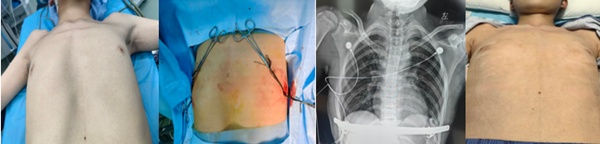

手術過程中,王偉醫(yī)生帶領團隊精準操作,采用 “三明治” 聯(lián)合矯形法:在患者胸腔內放置 NUSS 鋼板以支撐凹陷胸壁,同時在胸廓外皮下固定另一塊鋼板,通過內外雙重固定的方式,精準矯正胸壁的不對稱畸形。

術后復查顯示,小史的胸廓形態(tài)得到顯著改善,原本隆起、凹陷的胸壁恢復平整,駝背與脊柱側彎問題也得到有效緩解。更讓家人欣慰的是,小史的精神狀態(tài)明顯好轉,臉上重新露出笑容,對回歸校園、參與集體活動充滿了期待。